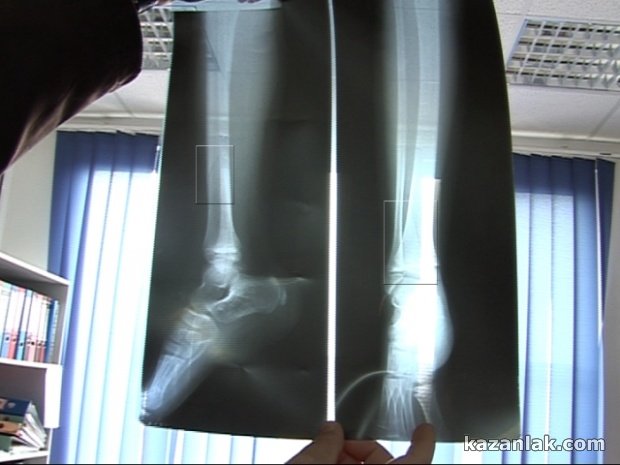

Момичето счупи крака си на 7-ми ноември преди обед в детската градина , когато закъсняло за занимания. Тогава, по думите на бащата на момченцето Красимир Дамянов и обясненията на самото дете , учителката В.Губеркова вдигнала Ралица нависоко, после я пуснала на земята. При падането момичето счупва левия си крак , в частта от глезена до тазобедрената става. Вече близо месец Ралица е в гипс и за нея се грижат родителите й.